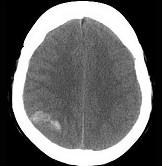

问题 男,37岁,头痛、头晕1年余,加重3天,CT检查如图所示,最可能的诊断为()

选项 A.脑出血 B.脑血管畸形并出血 C.脑膜瘤并出血 D.颅内动脉瘤 E.转移瘤并出血

答案 C